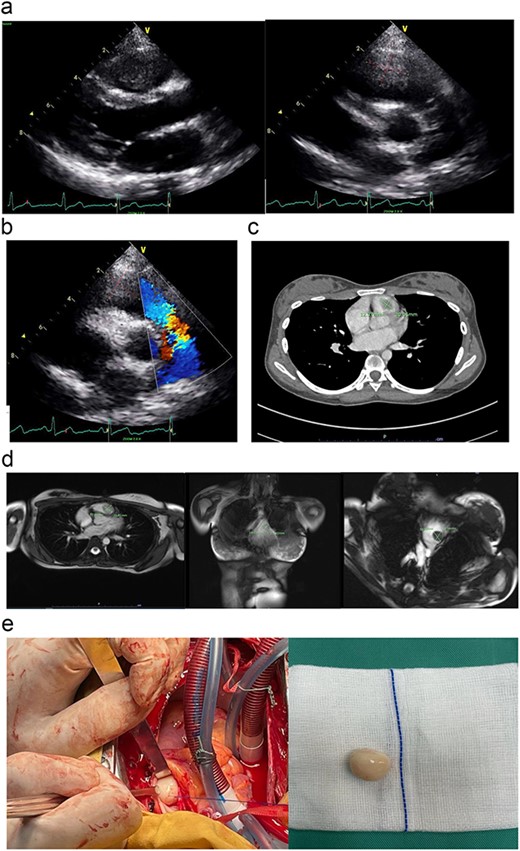

The initial echocardiography (ECHO) assessment findings were consistent with huge vegetation or a mass, obstructing the right ventricular outflow tract (RVOT) and abutting the pulmonary valve leaflet (Fig. 1a). She was initially treated for sterile infective endocarditis for a week duration until she was transferred to our cardiac centre for surgical intervention. After an expert opinion and multi-disciplinary consensus from the cardiologist, and surgeon, the diagnosis of right ventricular (RV) myxoma was confirmed using a multi-modality cardiac imaging such as cardiac computed tomography scan (CT scan) and cardiac magnetic resonance imaging (Fig. 1b–d). The patient was then counselled for surgical intervention.

(a) The parasternal long-axis view of transthoracic ECHO showing a well-defined mass, measuring ~ (2.0 × 2.0 cm) at the right ventricle. (b) The transthoracic ECHO colour flow Doppler showed significant pulmonary valve stenosis with potential Right ventricular outflow tract obstruction caused by the intracardiac mass. (c) The axial cut of a contrast-enhanced computed tomography (CECT) thorax showed a well-defined mass measuring ~ (2 cm × 2 cm) inside the RV. (d) The cardiac magnetic resonance imaging (MRI) confirmed the diagnosis of right RV myxoma by showing a well-defined hypointense mass measuring ~ (1.7 × 2.0 cm). (e) The tumour was identified and excised via a median sternotomy, bicaval cannulation, cardiopulmonary bypass, hypothermia, and cardiac arrested via antegrade cold-blood cardioplegia. The tumour was excised via a pulmonary arteriotomy approach. The tumour is well-defined, firm in consistency, and smooth surface. The size is ~ (2 cm × 2 cm).

We performed the surgical removal of RV myxoma via a primary median sternotomy. A cardiopulmonary bypass is achieved using a central aortic and bicaval cannulation. The heart was vented via the right superior pulmonary vein and an aortic root vent. The patient was then cooled down to moderate hypothermia at 30°C. An aortic cross-clamp and an antegrade cold-blood cardioplegia were given to achieve diastolic arrest. We approach the mass by performing a horizontal arteriotomy over the main pulmonary artery, to inspect the pulmonary valve leaflet and the RVOT (Fig. 1e). After the complete removal of the myxoma (Fig. 1e), the pulmonary valve was tested again before the arteriotomy closure. The patient was then rewarmed to normothermia, and the cardiopulmonary bypass was terminated. The chest was then closed in the usual manner after a post-operative transoesophageal ECHO confirmed a patent pulmonary valve and no residual mass.